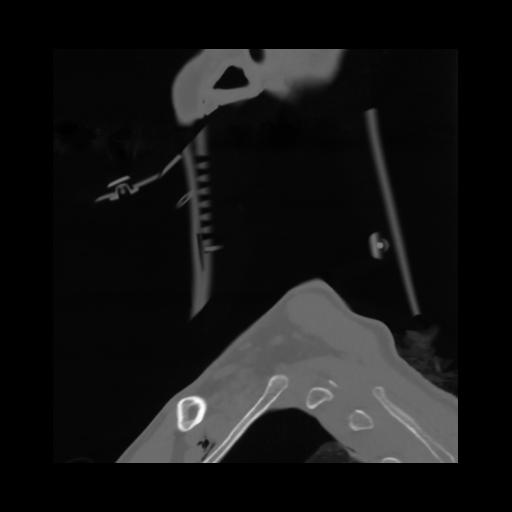

14 P.BLANDAS,,Sagittal,2.000,P.BLANDAS,Sagittal,